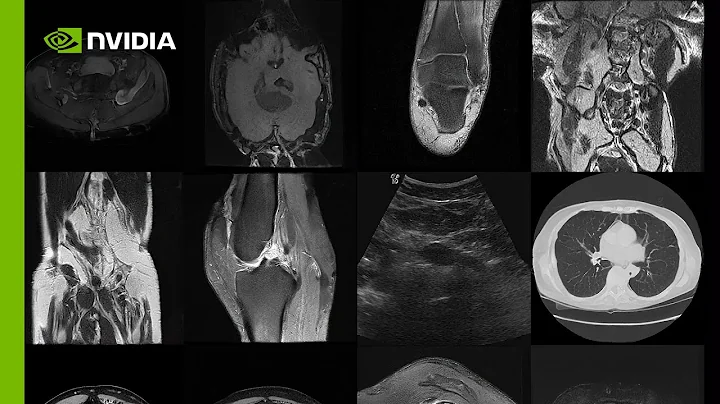

Genai Diffusion Models: A Tutorial On Score-based Generative Models W/ Medical Imaging Applications